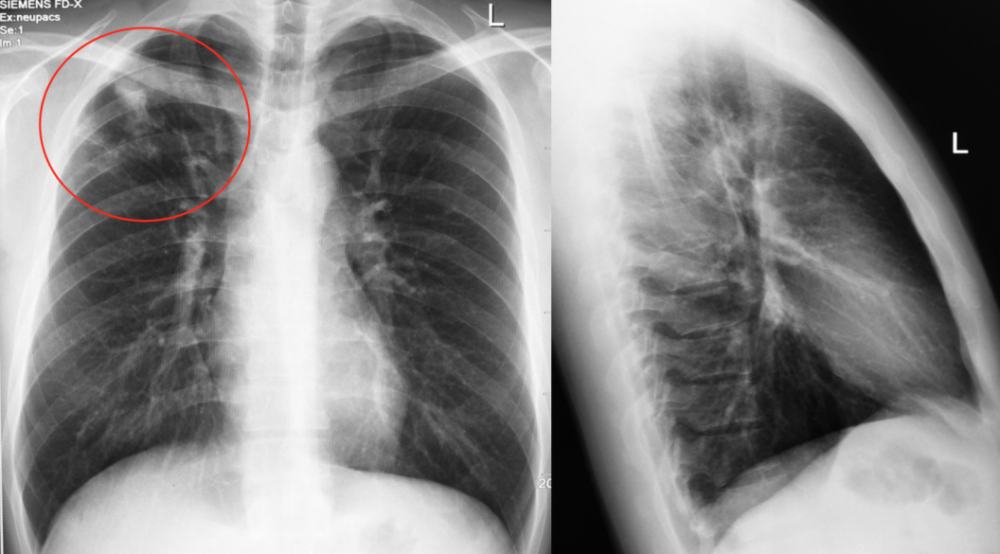

请大家帮我看看这个肺片有什么问题